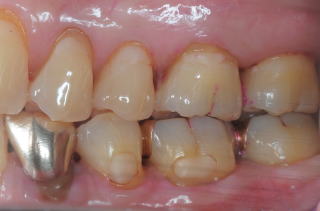

患者:83歳、女性

医療面接:子宮癌(全摘)、卵巣全摘、狭心症(1997年)、白内障手術(RL)(2009年)。帯状疱疹(体幹部、肋間神経支配部)(2010年)は当Clinicで治療。M.K.(胃癌)部分(1/2)開腹手術(2014年)。M.K.手術前の周術前口腔ケアでは、大学病院口腔外科受診時、担当医が口腔状態の良好状態に驚愕されたようだ。現在も毎月のS.P.T.(Supportive

Periodontal Therapy)を継続中。

(図15)2015年7月27日、83歳。高年齢と残存歯数ばかりが問題視されているが、歯槽骨の状態、歯肉、Pocketの状態を含めた歯周病を評価すべきである

歯周病治療38年経過:83歳(女性)残存歯数28本